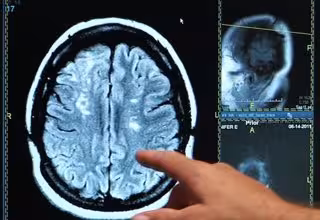

Arrojan luz sobre la recuperación del cerebro tras un ictus

Ictus, derrame cerebral, cerebro

El accidente cerebrovascular es una de las tres principales causas de muerte en Canadá y lleva a la discapacidad permanente en aproximadamente la mitad de los supervivientes. Durante un accidente cerebrovascular isquémico, hay un bloqueo del flujo sanguíneo que produce la muerte celular en un área específica o el cerebro.